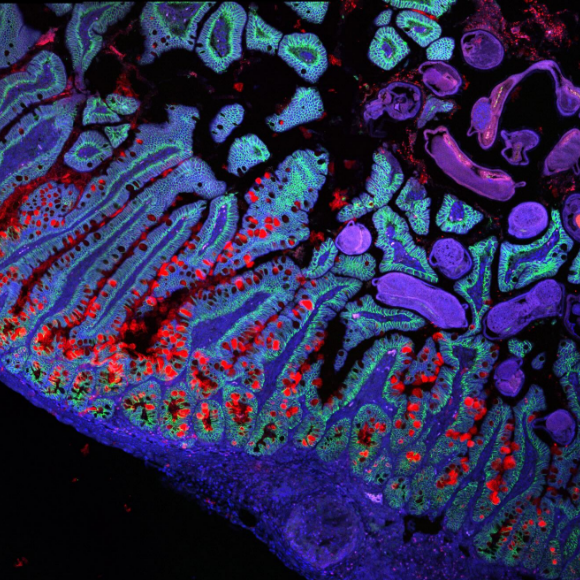

העכברים שעליהם נערך הניסוי עברו טיפול כדי שידמו חולי פיברוזיס ריאתי בשתי דרכים שונות. העכברים בניסוי הראשון קיבלו לאורך ארבעה שבועות תרופה כימותרפית, כך שתגרום להתפתחות פיברוזיס ריאתי. לאחר ארבעת השבועות, החוקרים הפסיקו את מתן התרופה והשתילו אצלם תאי אב ריאתיים, שהופקו מריאות של עכברים בריאים. תאי האב המושתלים הכילו חלבון אדום, שאִפשר לזהות אותו בקלות אצל העכברים שעברו את ההשתלה.

תאי האב המושתלים נקלטו בריאות בקלות, ואף לא היה צורך לפגוע בתאים המקוריים בקרינה, כמו במחקרים הקודמים. כמו כן, שמונה שבועות לאחר ההשתלה התאים המושתלים התמיינו כהלכה, התפתחו לתאי הריאה מהסוגים הרצויים ויצרו נאדיות חדשות. לעכברים שעברו את ההשתלה היו ריאות פחות מצולקות, ותפקודי הריאות שלהם הגיעו לכדי 75 אחוזים מתפקודי הריאות של עכברים בריאים. לעומת זאת, אצל העכברים שטופלו בתרופה הכימותרפית אך לא קיבלו תאי אב בריאים נמדדו תפקודי ריאות של כ-40 אחוזים.